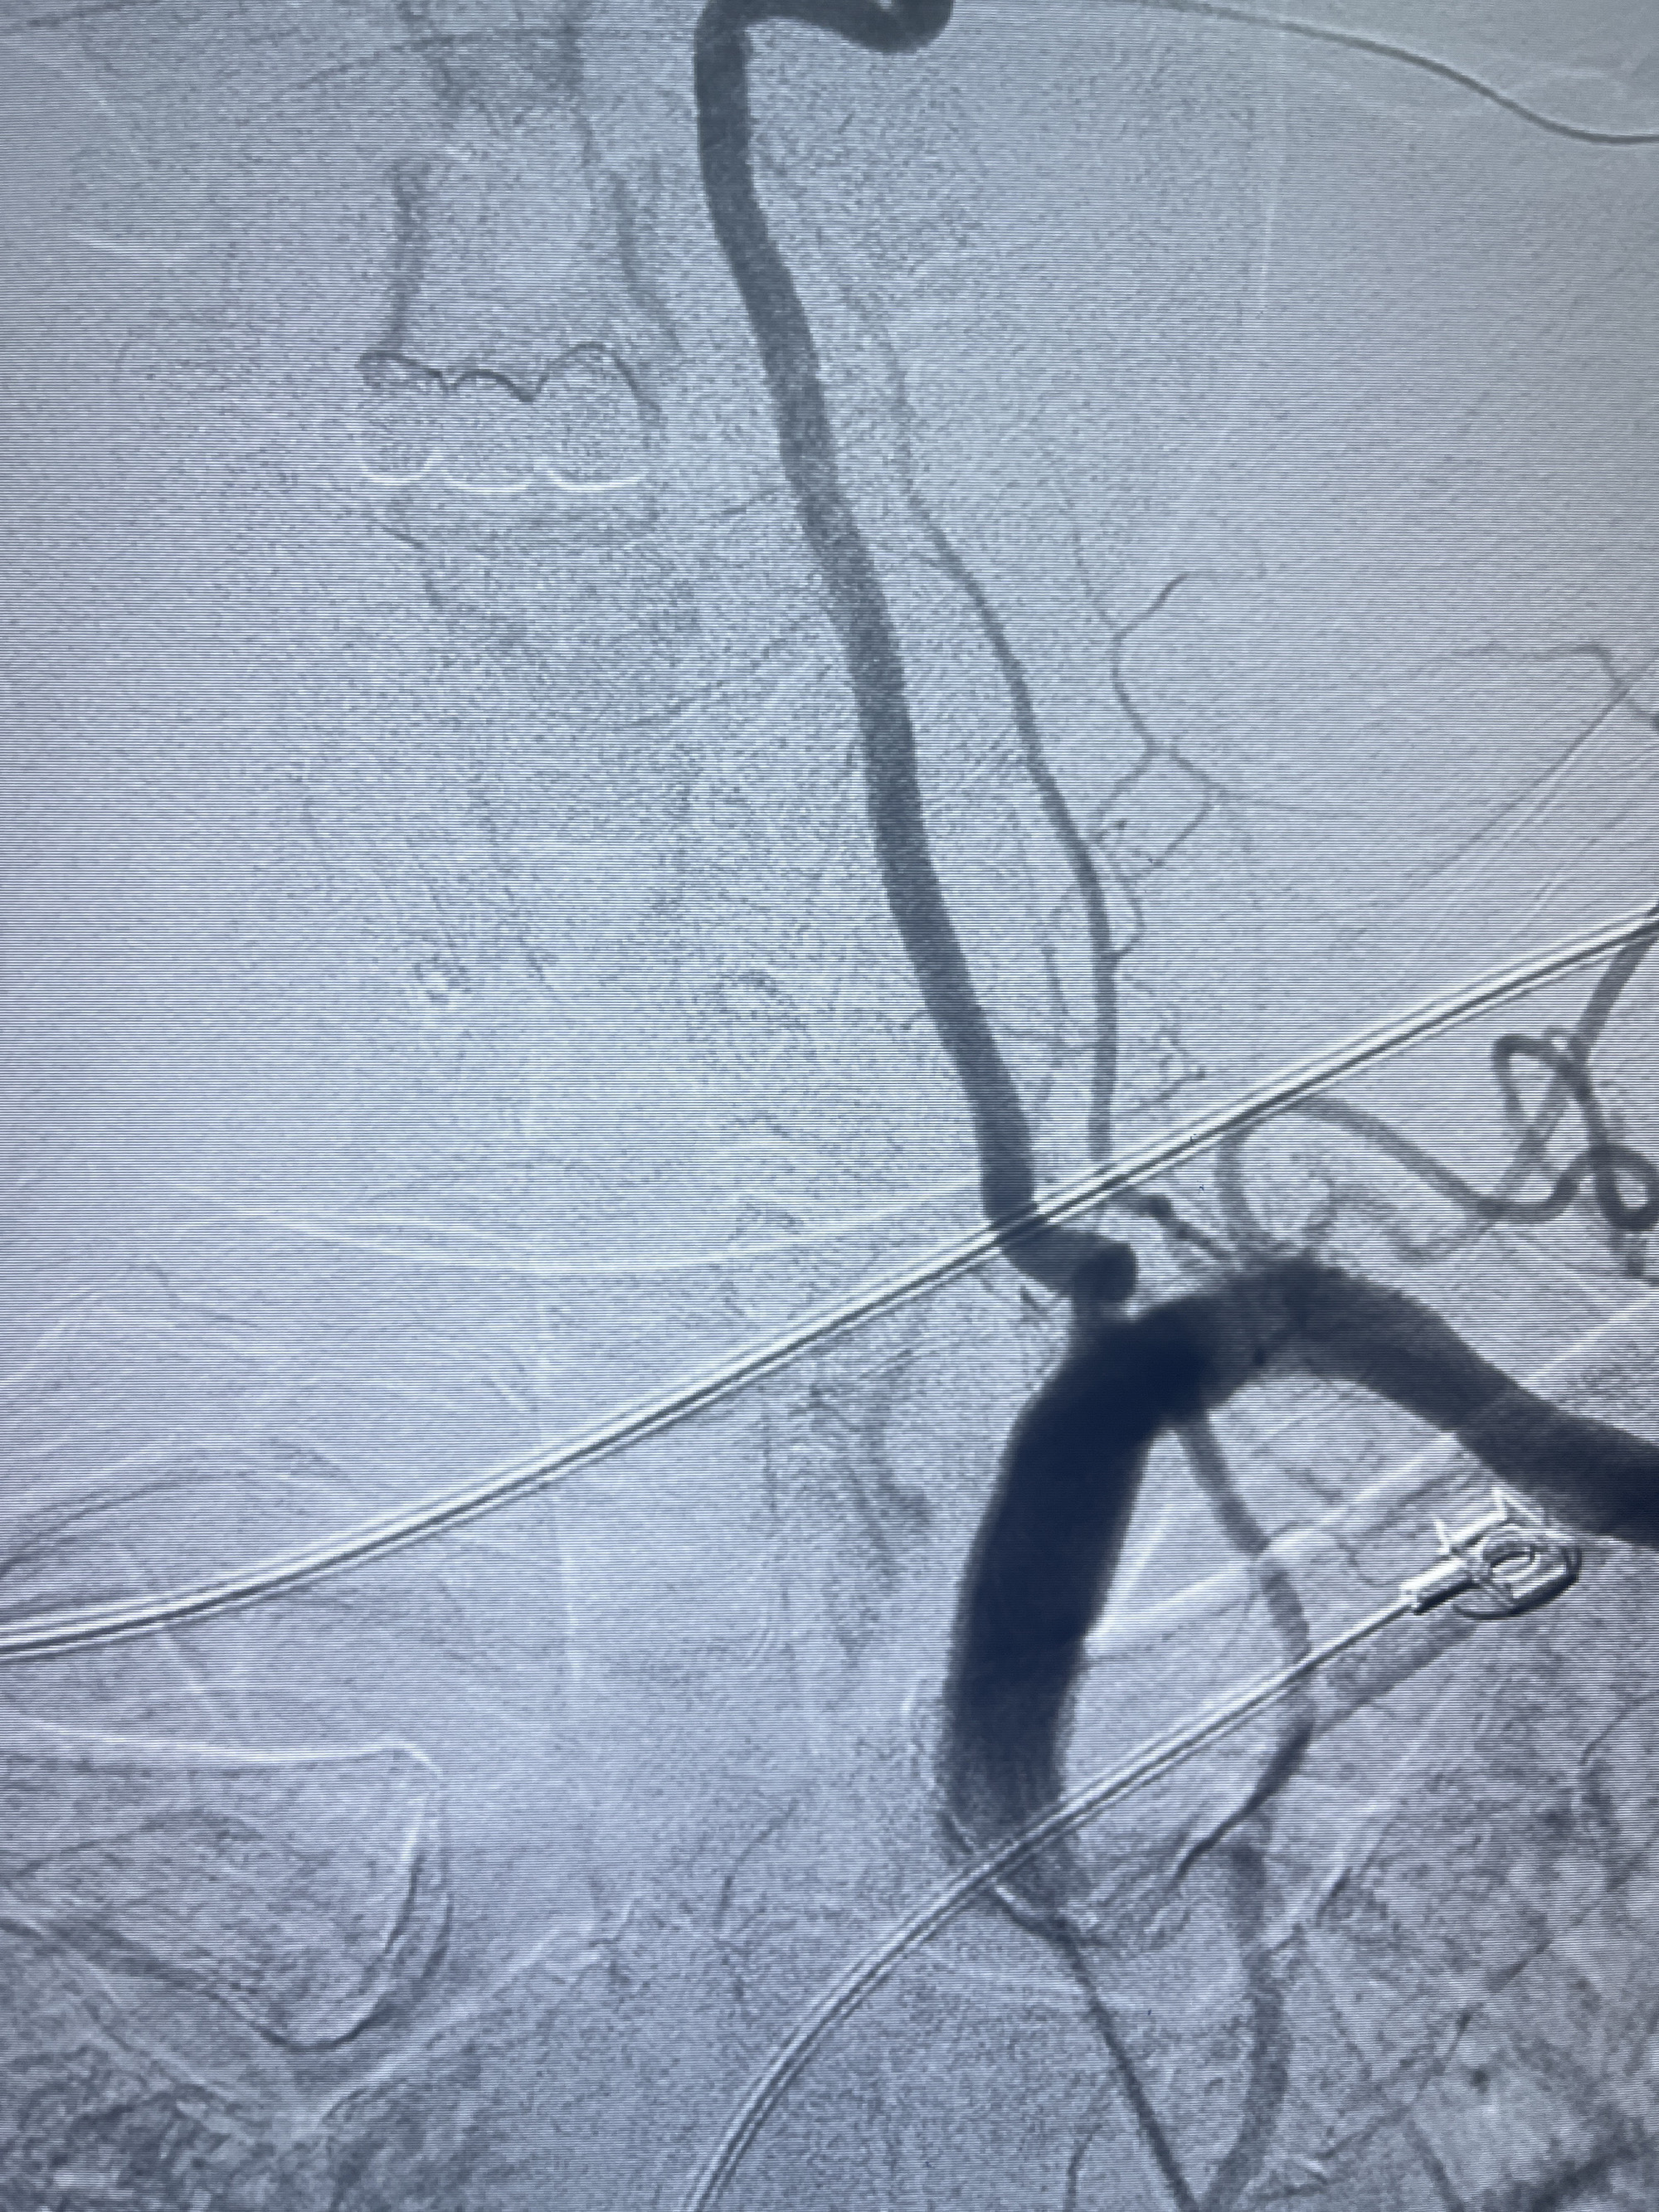

202.04.28脑血管造影:右侧大脑后动脉远段闭塞,右侧椎动脉V4段可见“囊状造影剂填充影”,大小7.64*7.65mm,可见PICA由动脉瘤发出;